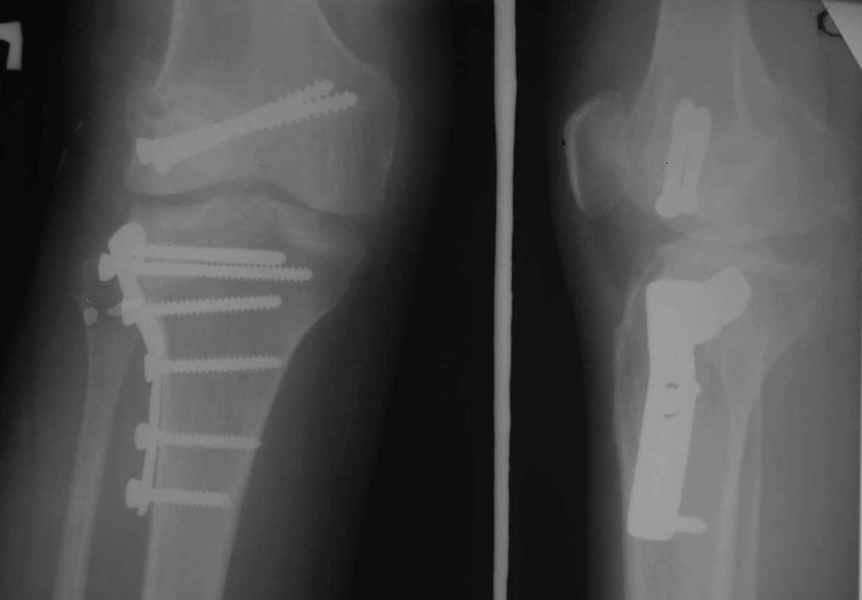

Как вариант решения прогрессирующей вальгусной деформации коленного сустава я бы предложил косую остеотомию дистального отдела бедра с фиксацией пластиной и компрессирующим винтом.

Взгляните на снимки , может быть это вам поможет.

Около 5 лет применяю этот тип дистальной остеотомии бедра для коррекции механической оси Н/К ( более 20 случаев) - достаточно эффективная операция.

Уважаемый Евгений ! Спасибо за ответ, но мне представляется, что в нашем случае основной проблемой является не столько прогрессирующий вальгус конечности, сколько несросшийся перелом мыщелка бедра и дефект мыщелка большеберцой кости - вероятно первичная репозиция выполнялась без пластики.

На своем горьком опыте убедился, что синтезировать мыщелковые импрессионные внутрисуставные переломы б\б кости без костной пластики - дело неблагодарное, рецидивируе деформация, мыщелок всегда *проваливается*. Чистые split type переломы можно ограничиваться и одной только межфрагментарной компрессией.

Может стоит сначала добиться сращения наружного мыщелка бедра( костная пластика) и коррекции оси?

Мне представляется, что прогрессирующий вальгус и обусловлен несросшимся переломом мыщелка бедра (томограммы -зона межфрагментарного склерозирования), а циклические нагрузки на сустав во время ходьбы усугубляют ситуацию. Как вы думаете, в этой ситуации насколько вероятен риск развития аваскулярного некроза мыщелка бедра?